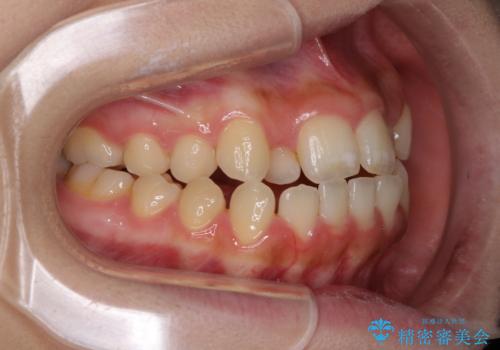

上顎骨を拡大したことで、下顎の歯列を上顎が受け入れられるようになりましたが、インビザラインでは咬み合わせを改善させることができなかったため、ワイヤー矯正にて仕上げることとしました。

ワイヤーを使用したものの、上下前歯のオープンバイトがなかなか改善されませんでしたが、患者希望により治療終了となりました。